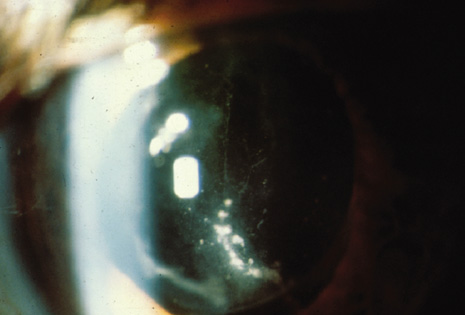

DELAYED-ONSET OR CHRONIC POSTOPERATIVE ENDOPHTHALMITIS

In this endophthalmitis category, patients may present weeks to months after cataract extraction, often with mild-to-moderate inflammatory signs and a chronic indolent course.16,94 P. acnes, a gram-positive, anaerobic pleomorphic rod, is a common causative organism in this category. The clinical P. acnes syndrome of delayed-onset pseudophakic endophthalmitis, first described by Meisler and associates94 in 1986, typically includes granulomatous inflammation with large keratic precipitates (Fig. 6) and a white intracapsular plaque that has been shown to be composed of organisms mixed with residual lens cortex. When infection with this slow-growing organism is suspected, anaerobic cultures of both the aqueous and vitreous should be obtained and held at least 2 weeks.

Fig. 6. Delayed-onset pseudophakic endophthalmitis. Left: This patient presented with granulomatous uveitis, vitritis, and a white plaque within the capsular bag, which is characteristic of infection caused by Propionibacterium acnes. Right: Marked granulomatous keratic precipitates are occasionally seen in endophthalmitis caused by P. acnes.